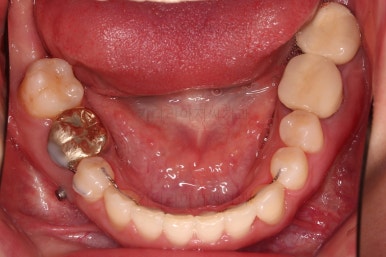

부산치과교정 키다리아저씨치과 초진 시 입안의 모습입니다.

확연히 좌우의 삐뚤어진 정도가 차이나죠.

덧니도 좌측(사진에서 보면 오른쪽) 위아래만 있는 상태고요.

좌측으로 삐뚤어져서 앞니도 좌측으로 쏠려 있는 상태였습니다.